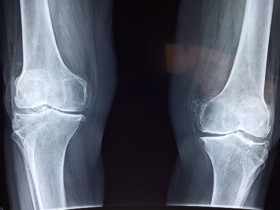

درمان شکستگی استخوانی در فضا به چه صورت است؟

محققان به تازگی به این نتیجه رسیده‌اند که میزان جاذبه موجود در سطح زمین، این سیاره را به بهترین مکان در هستی برای درمان شکستگی‌های استخوانی تبدیل کرده است.

محققان دانشگاه میسوری آمریکا در تحقیق خود بر این موضوع تمرکز کرده‌اند که وضعیت استخوان‌ها و غضروف‌ها در فضا چگونه است.

تیم محققان دانشگاه میسوری تصمیم گرفتند این موضوع را بررسی کنند که تشکیل غضروف در شرایط جاذبه ضعیف چگونه خواهد بود و شرایط بی‌وزنی مانند آنچه در ایستگاه فضایی بین‌المللی وجود دارد چه تاثیری بر ترمیم استخوانی خواهد داشت.

محققان دانشگاه میسوری با استفاده از تجهیزات ایجاد جاذبه صفر که متعلق به "سازمان فضایی آمریکا"(ناسا) است، موفق شدند رفتار سلول‌های بنیادی غضروف را در نبود جاذبه بررسی کرده و آن را با نحوه تکثیر این سلول‌ها در شرایط جاذبه زمین مقایسه کنند.

در طی این بررسی‌ها مشخص شد که این سلول‌ها روند تکاملی بسیار بهتری را در شرایط جاذبه زمین طی می‌کنند و استفاده از تجهیزاتی که جاذبه زمین را شبیه‌سازی می‌کنند می‌تواند در شرایط بی‌وزنی به رشد این سلول‌ها کمک کند هر چند که نتیجه مانند شرایط عادی نخواهد بود.

نتیجه این تحقیق نشان می‌دهد که زمین بهترین مکان برای درمان آسیب‌های استخوانی است و فضانوردان هر چقدر بتوانند بیشتر در شرایط مشابه زمین قرار بگیرند، بهتر می‌توانند از سلامتی خود محافظت کنند و بعلاوه این موضوع چالشی جدی برای زندگی در فضا محسوب می‌شود.